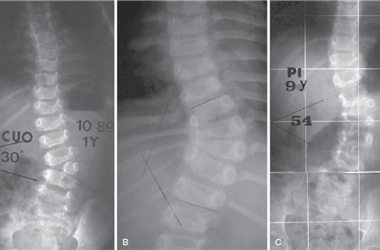

德康醫療脊柱畸形治療解決方案

德康醫療與北京協和醫院仉建國教授團隊合作研發的VSS脊柱專用矯形器械,功能強大,靈活應對脊柱復雜三維矯形手術。